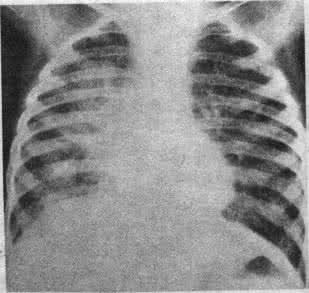

小叶性肺炎图片x片,小叶性肺炎切片图片

② 小叶性肺炎

小叶性肺炎x片

小叶性肺炎